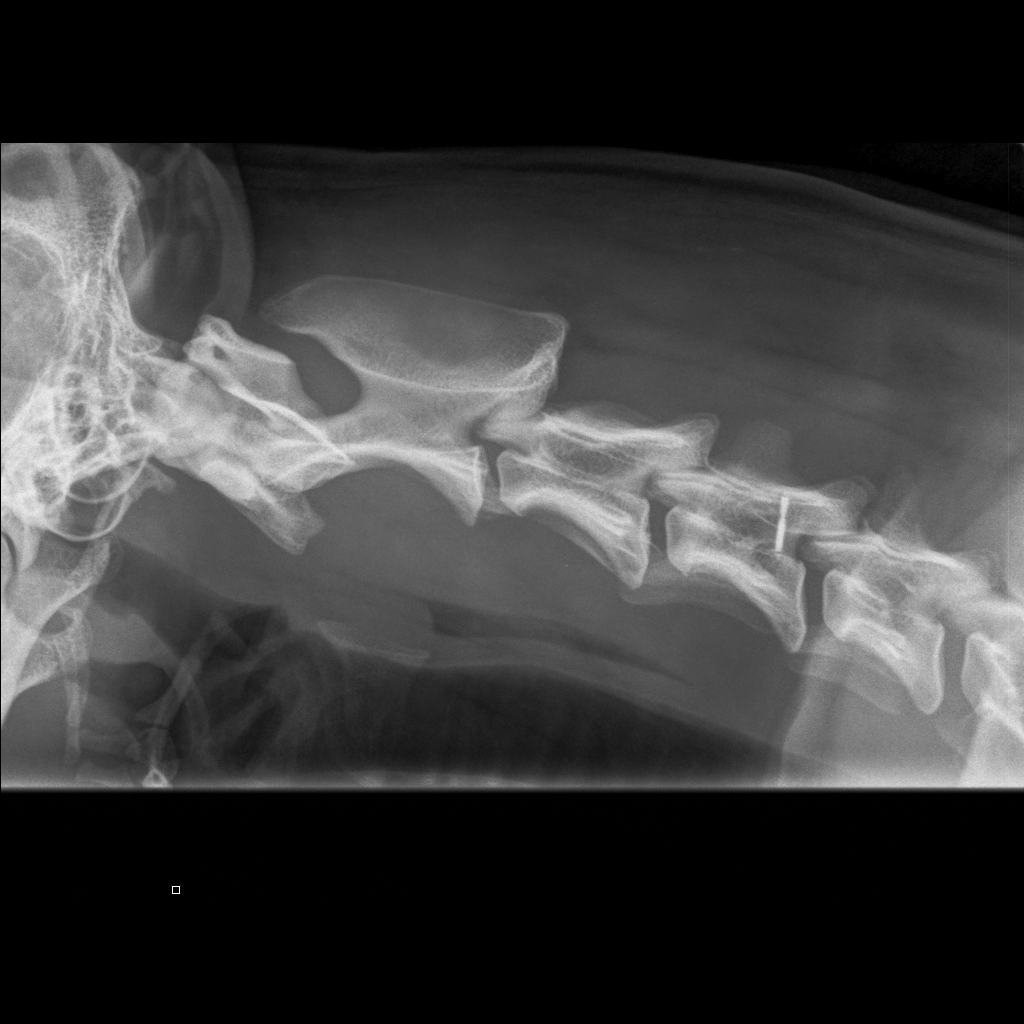

Niskasta otettu taivutuskuvat 17.10.14:

kaularanka1

kaularanka2

kaularanka3

Quti viety lääkäriin, koska vingahtelee kääntäessän päätään. Koko selkä kuvattiin, ei muutoksia. Oireiden jatkuessa kaularanka

magneettikuvattiin. Kuvanneen eläinlääkärin mielestä Nomilla on välilevyrappeuma ja kaikki harrastaminen mietittävä uudelleen.

Halusimme toisen mielipiteen Timo Talviolta, joka halusi ottaa Nomin kaularangasta taivutuskuvat. Talvion mukaan kyseessä ei ole

välilevyrappeuma vaan taivutuskuvissa näkyy kaularangan nikamien 5 ja 6 välillä liukuma. Lääkekuurin ja levon jälkeen voi

harrastamista jatkaa normaalisti. Talvion lausunto:"Kyse on nikamien välisestä "löysyydestä". Selkärangan rakenteelliset

viat ovat pääsäänöisesti perinnöllisiä, mutta tällainen lievä nikamien välinen liikkuvuus ei sellaisenaan ole perinnöllistä,

toki perintötekijät voivat altistaa tämänkaltaisen tilan kehittymiseen."